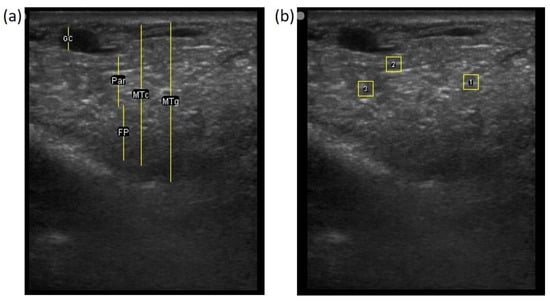

The image processing was undertaken using ImageJ software [28] as used by Abràmoff et al. [29]. The scales between pixels and millimetres were calculated based on the number of pixels, the scanning depth (mm), and the transducer width (mm) (Figure 4). This method relies on the ability of the operator to interpret and identify lines on the images. To standardize the assessment compartment depth, drawing templates were created for each time point as used by Molenaar et al. [30] and included four representative images from four different yearling ewes with and without the lines drawn for each compartment (Appendix A). The total depth of mammary gland conservative (MTc) was the smallest likely demarcation (abdominal wall) of the mammary gland (Figure 5a), and total depth of the mammary gland generous (MTg) was the largest likely demarcation of the mammary gland visible on the image [30] (Figure 5a). The MTc, MTg, fat pad (FP), parenchyma (PAR), and gland cistern (GC) depths were estimated at the deepest point for each sub-compartment, excluding the skin layers, using the straight tracer (Figure 5a) and were expressed in millimetres.

Figure 5.

(a) Demonstration of delimitations of the mammary total depth conservative (MTc) and generous (MTg), mammary gland cistern (GC), parenchyma (PAR) and the fat pad (FP) and (b) Demonstration of randomly positioning of regions of interest (1, 2, 3) in the parenchyma.

To assess the development of the parenchyma at P107, L29, and L100, three regions of interest (ROI; [26]) were randomly drawn in the parenchyma area, each square measured 6.7 mm2 (Figure 5b). The brightness of each pixel corresponded to echogenicity and was numerically represented on a scale of 256 levels of grey [31]. Echogenicity is defined as the capacity of tissues to interact and reflect the sound waves of the transducer [32]. This capacity varies with tissues, i.e., liquids have very low echogenicity [32] and fat has greater echogenicity but attenuates as the depth increases [30].